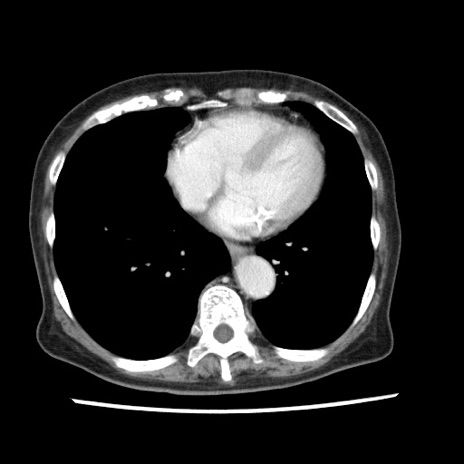

症例1(横断像)

【症例】80歳代女性

【主訴】腹痛

【現病歴】8時間前から腹痛あり来院。

【既往歴】糖尿病、脂質異常症、子宮体癌にて子宮全摘術

【身体所見】意識清明・会話良好だが腹痛で苦悶様、全腹部にわたって反跳痛と圧痛あり

【データ】WBC 13600、CRP 0.14、LDH 224、CK 90